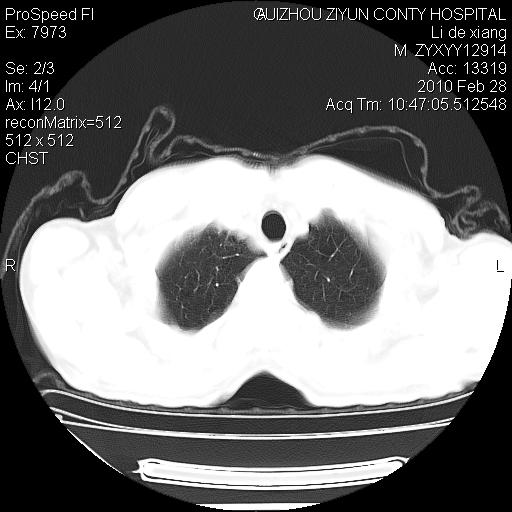

标题: CT24776:男 71Y 咳嗽咳痰胸痛两月,伴声音嘶哑。 [打印本页]

标题: CT24776:男 71Y 咳嗽咳痰胸痛两月,伴声音嘶哑。

左侧中央型肺癌伴左肺上叶阻塞性肺炎及节段性不张可能性大,建议纤支镜检查!

左侧中央型肺癌伴左肺上叶阻塞性肺炎及节段性不张可能性大,建议纤支镜检查!纵隔淋巴结转移.

左肺门部肿块,伴左上肺斑块影,周边模糊,支持左肺中央型肺癌伴节段性不张及阻塞性肺炎,结合支气管镜检查。

左上叶支气管狭窄,阻塞性病变,肺门肿块,纵隔及肺门淋巴结增大,中央性肺癌